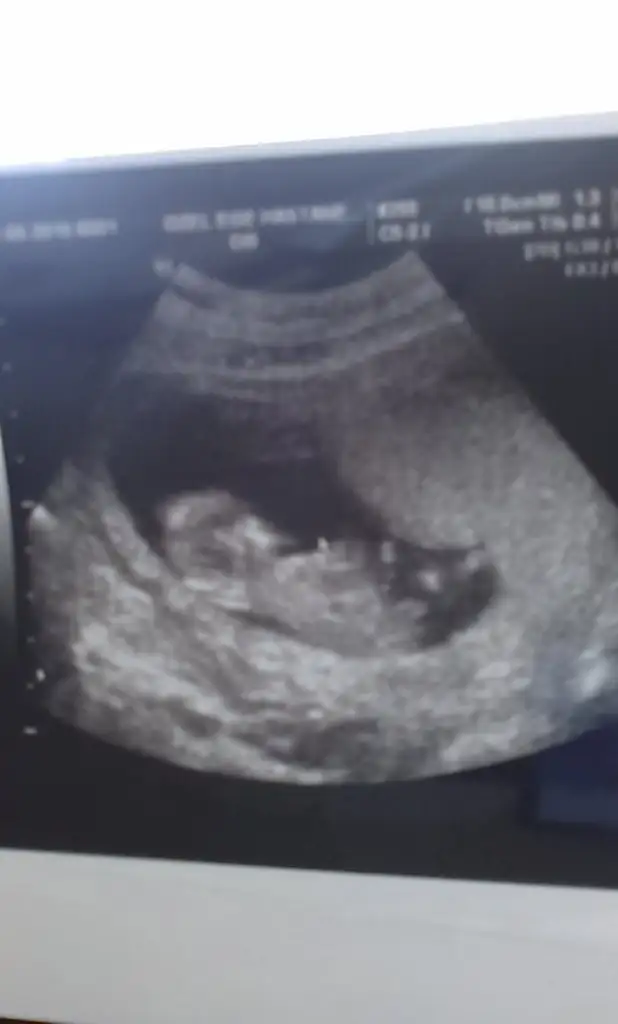

yorum yaparmısınız arkadaşlar .iki yeni resim daha yükledim lütfen yorumlarınızı bekliyorum

20 haftalığım bende hala öğrenemeynlerdenim .yorum yaparmısınız arkadaşlar .